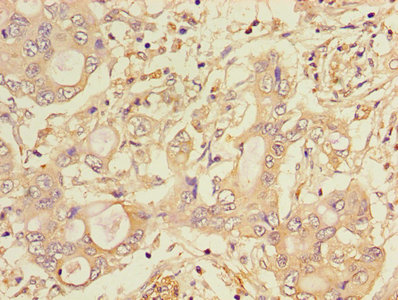

Immunohistochemistry of paraffin-embedded human pancreatic cancer using CSB-PA006184LA01HU at dilution of 1:100